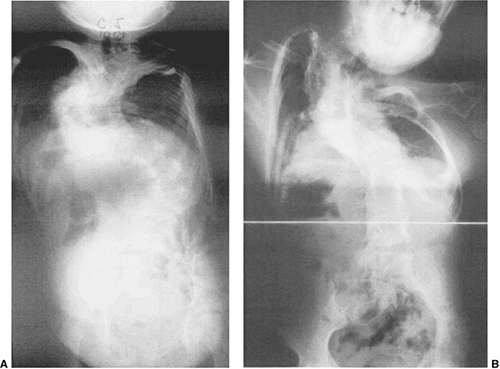

Figure 19.1 A:

Classification of congenital scoliosis. Failures of segmentation or formation, singly or in combination, describe nearly all congenital scoliosis. Hemivertebrae can be classified as fully segmented, semisegmented, or nonsegmented. When deficiencies of vertebrae above and below compensate for the hemivertebra, it is described as incarcerated. The growth potential of hemivertebrae can be estimated by the presence and thickness of superior and inferior endplates. A unilateral bar opposite a fully segmented hemivertebra is very likely to progress with growth. B: Classification of congenital kyphosis. Many instances of congenital scoliosis contain elements of congenital kyphosis. Nearly all congenital kyphotic deformities are progressive and are best treated by early in situ posterior fusion if the patient is less than 5 years and the curve is less than 50 degrees. If untreated, progressive kyphotic deformities with failure of formation may produce paraplegia. (A: From McMaster MJ, Ohtsuka K. The natural history of congenital scoliosis. A study of two hundred and fifty-one patients. J Bone Joint Surg Am 1982;64(8):1128–1147, with permission. B: From McMaster MJ, Singh H. Natural history of congenital kyphosis and kyphoscoliosis. A study of one hundred and twelve patients. J Bone Joint Surg Am 1999;81(10):1367–1383, with permission.) |